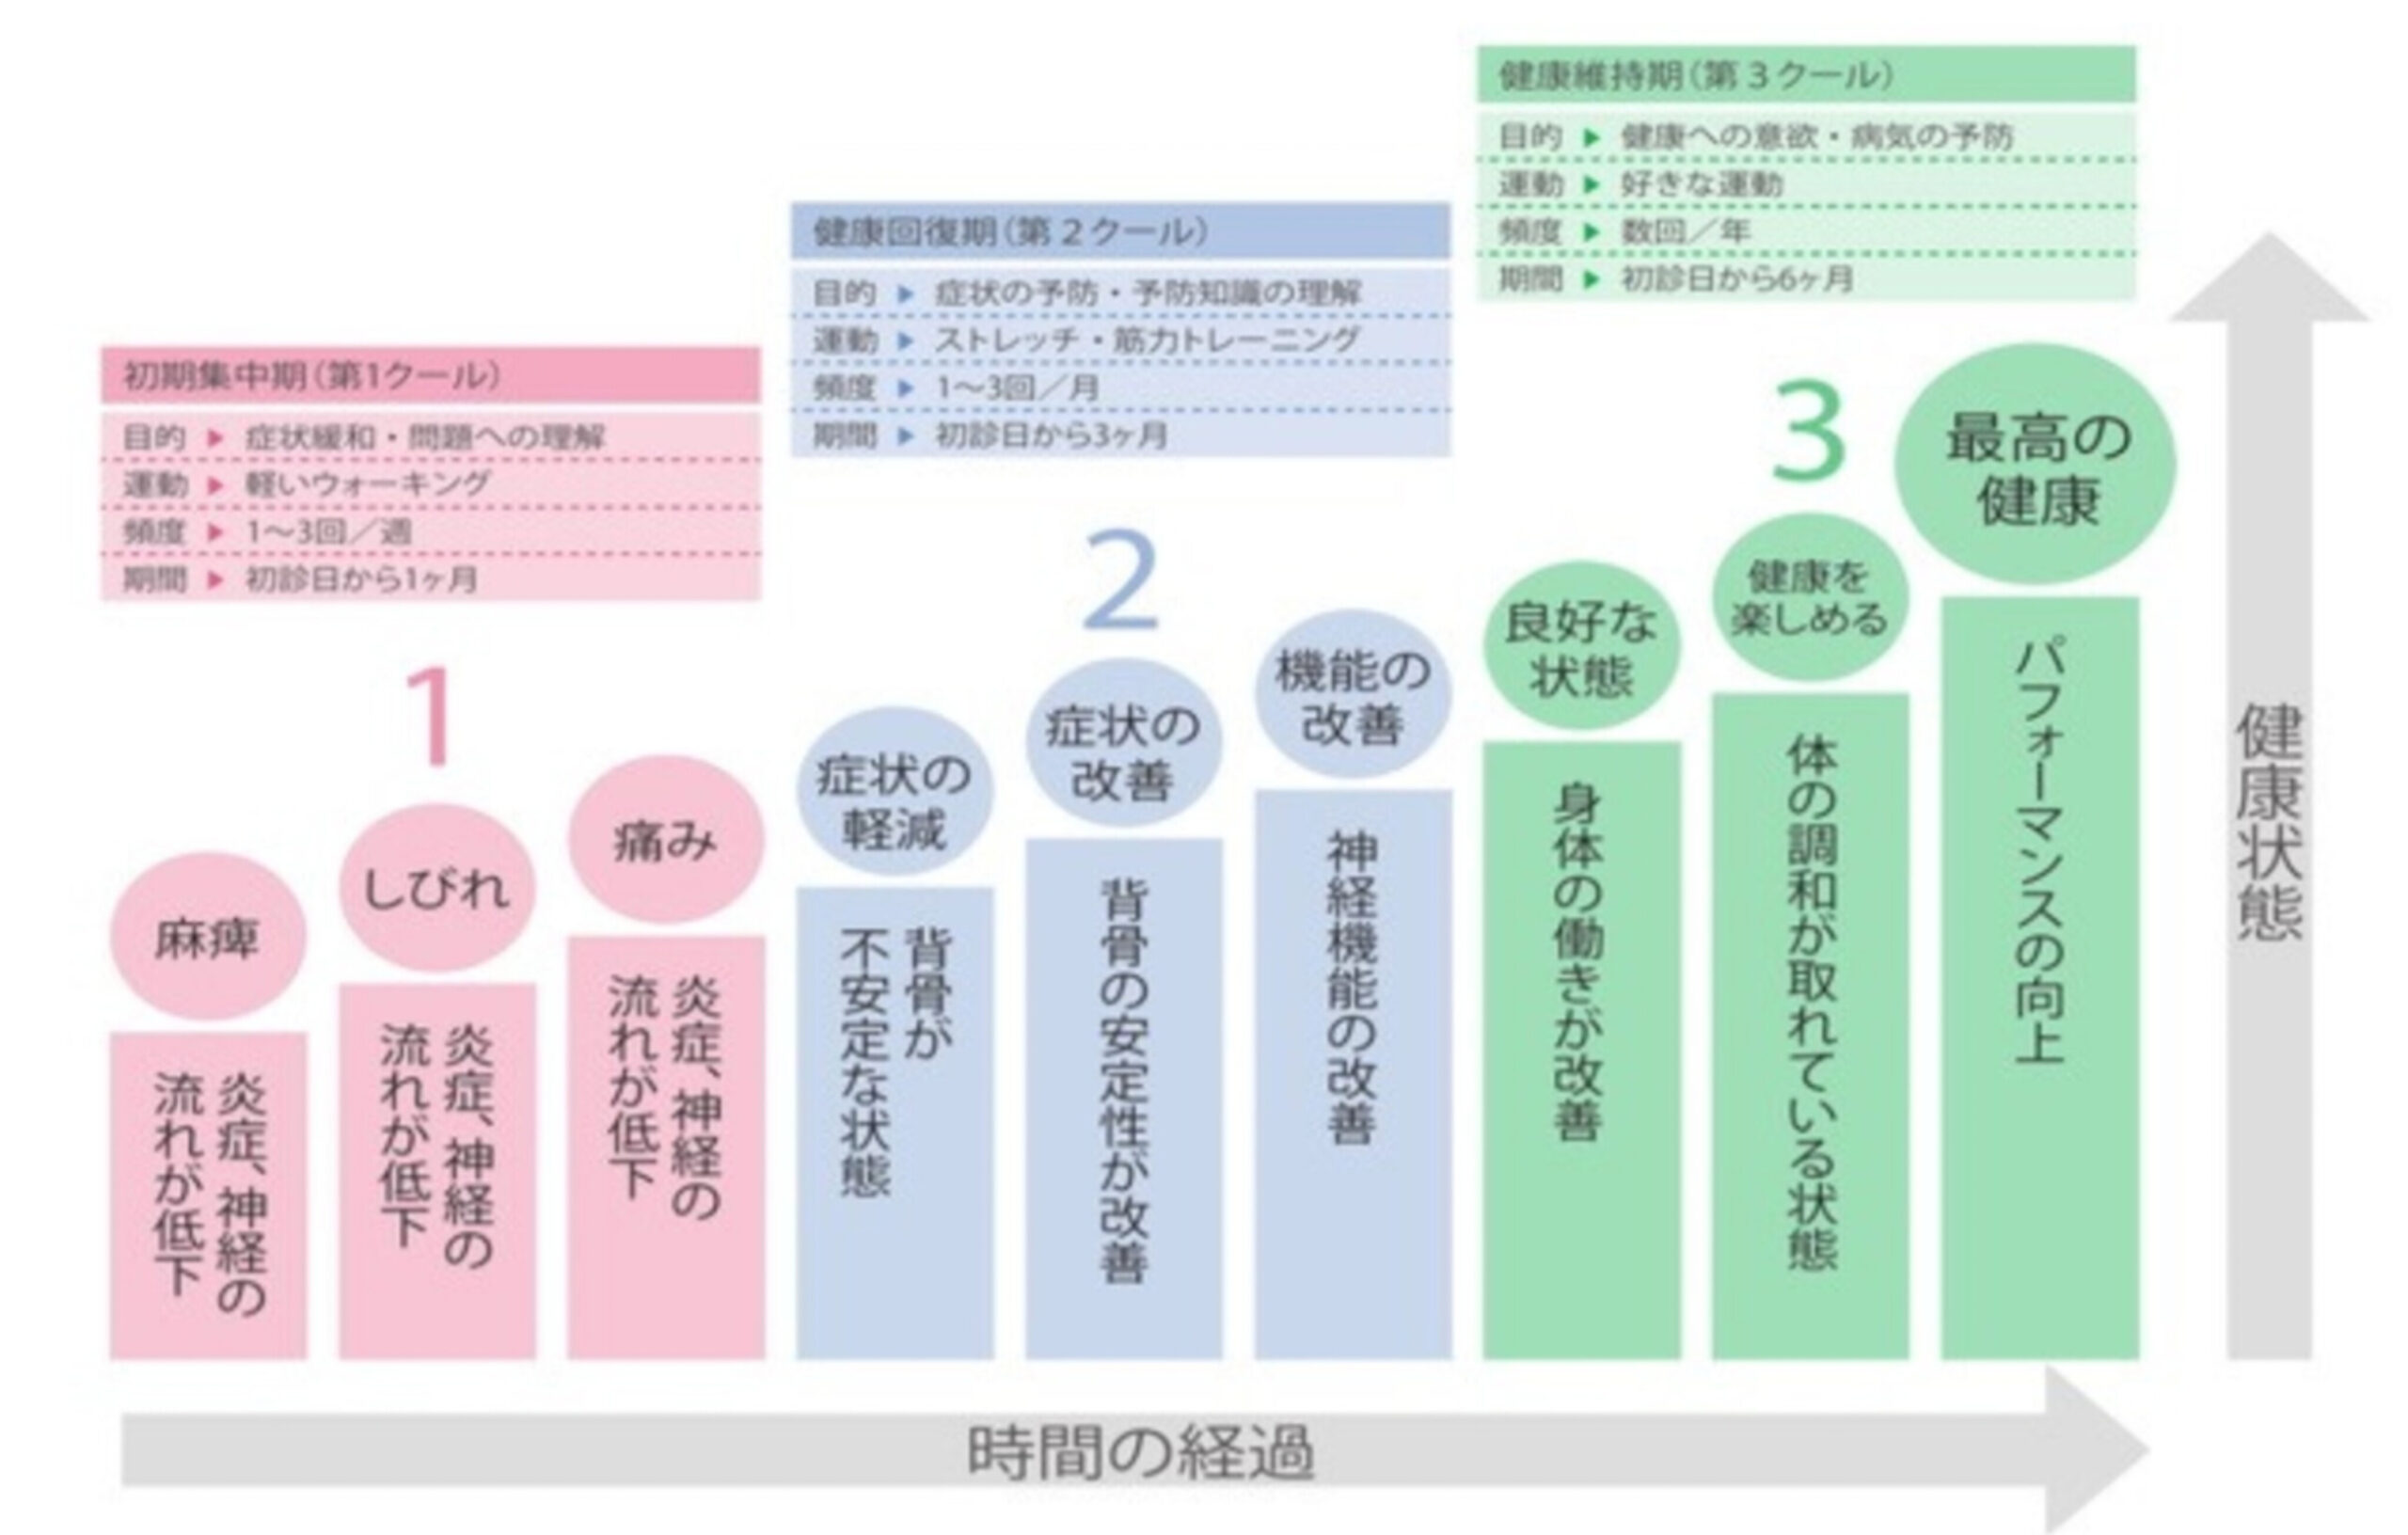

初期集中期

症状の緩和を主な目的とした段階。 頻度高く来院することで、身体が本来の機能を取り戻す基盤を整えます。

健康回復期

症状が和らいだ後、脊椎の構造的な改善を定着させる段階。 再発を防ぎ、身体のバランスを安定させることを目指します。

健康維持期

身体の機能とバランスを高い水準で維持するための定期ケア。 自然治癒力を持続的に引き出し、健康な日常をサポートします。